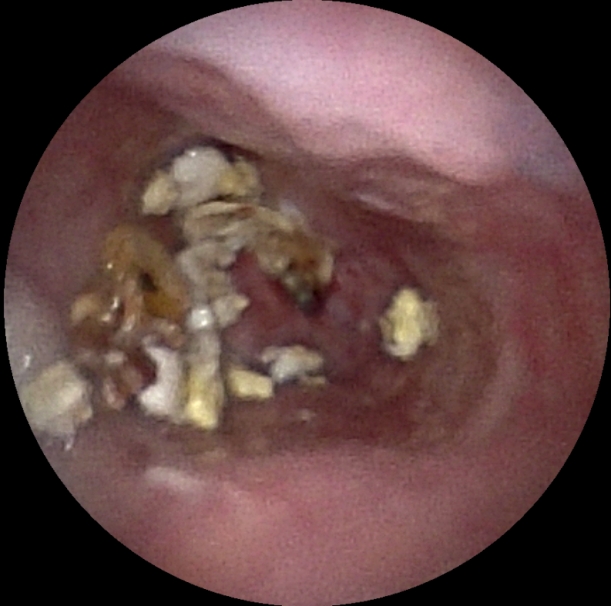

术前、术中、完成造瘘的食管

食管癌发展至中晚期,常因肿瘤浸润导致食管重度闭塞,即使是超细内镜也难以通过,患者很容易陷入不能进食、难以饮水的绝境,属于临床极为棘手的急症。传统治疗多在X射线透视下放置导丝、逐级扩张并完成造瘘,虽能解决营养通道问题,但存在操作盲目性,且医患双方均会受到射线辐射,医护也需要穿戴厚重铅衣开展手术,既增加手术风险,也不利于长期健康防护。